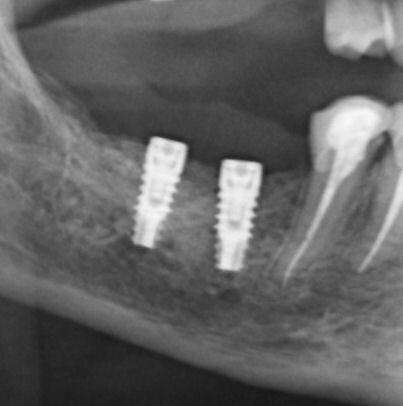

Figg. 15, 16_Controllo radiografico post-implantare e follow-up ad 1 anno.